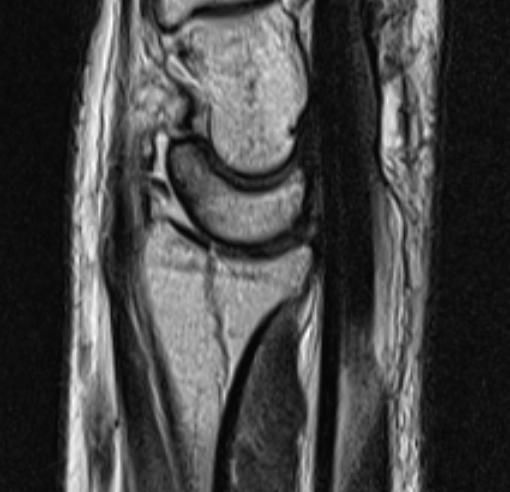

손목 요골 원위부 골절 문의드립니다.

약 3주전 넘어지는 사고로 손목 골절 진단 받고 1주 반깁스 후 통깁스 치료 중입니다.

아래는 사고 당시 X-ray 와 CT, MRI 사진입니다.

• 1번 째 사진

요골 원위부 골절은 골절의 모양, 전위 정도, 관절면 침범 여부에 따라 치료방침이 달라집니다.

엑스레이 및 CT에서 저누이가 심하지않고 관절면에 영향이 없다면 보존적 깁스 치료로도 충분히 잘 붙는 경우가 많습니다. 다만 고령, 골다공증, 분쇄골절, 관절면 불일치 시엔 추후 통증 기능장애 가능성이 있어 수술이 고려됩니다.

• 올리신 사진 세 장을 놓고 진료를 받으신 병원들만큼 자세하게 파악하고 정확한 판단을 내려드릴 수는 없습니다. 사진들을 보았을 때에는 변형이 심하게 생기거나 해 보이지 않기 때문에 손목 가동범위에 문제가 있거나 신경 손상 등을 의심할만한 소견이 없다면 수술적 치료 없이도 회복이 가능할 수도 있겠다 추측해볼 수도 있겠습니다. 그렇지만 앞서 언급하였듯 정확히 어떻다 이야기 하기는 어렵습니다.